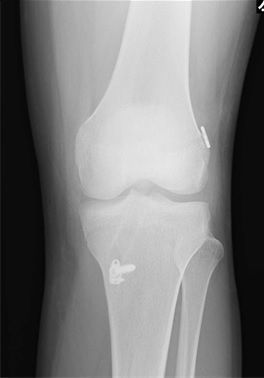

レントゲン所見

| 手術前 | 手術後 |

| 骨傷・関節変形なし | 異常なし |